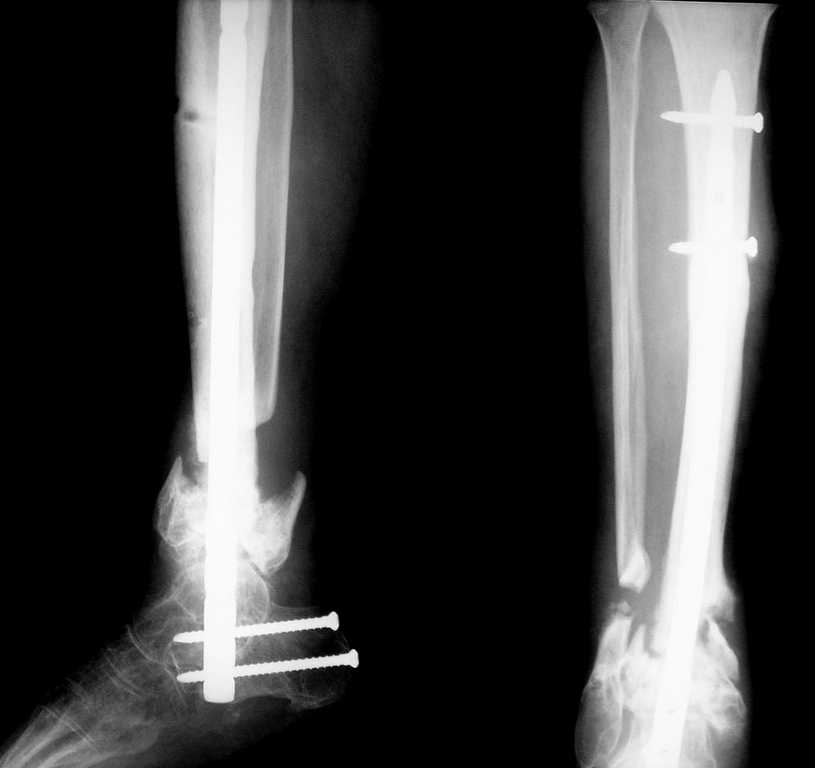

Вот что в итоге получилось. Вопрос по поводу нагрузки: может сразу дать? и зря я поставил статический винт?

DFN "остеомед",под правую ногу взяли левый гвоздь,с учётом нормального вальгирования пяточной кости. Хотел поставить HAN со спиральным лезвием,специально созданный для этого, но из-за организационно-технических моментов не удалось. Ну да в следующий раз....

Алексей, а в каком положениии стопы получилась фиксация? Не в эквинусе ли стопа??

Движений в голеностопном суставе совсем не было, устранить эквинусную установку можно было только за счет угла открытого кпереди в зоне ложного сустава. Поэтому выбирая между восстановлением оси конечности и эквинусом я выбрал ось.Возможно эквинус компенсирует укорочение 2,5 см (которое при динамизации увеличится). Наверно не так уж и страшно, если больной теперь обречён на обувь с каблуком?